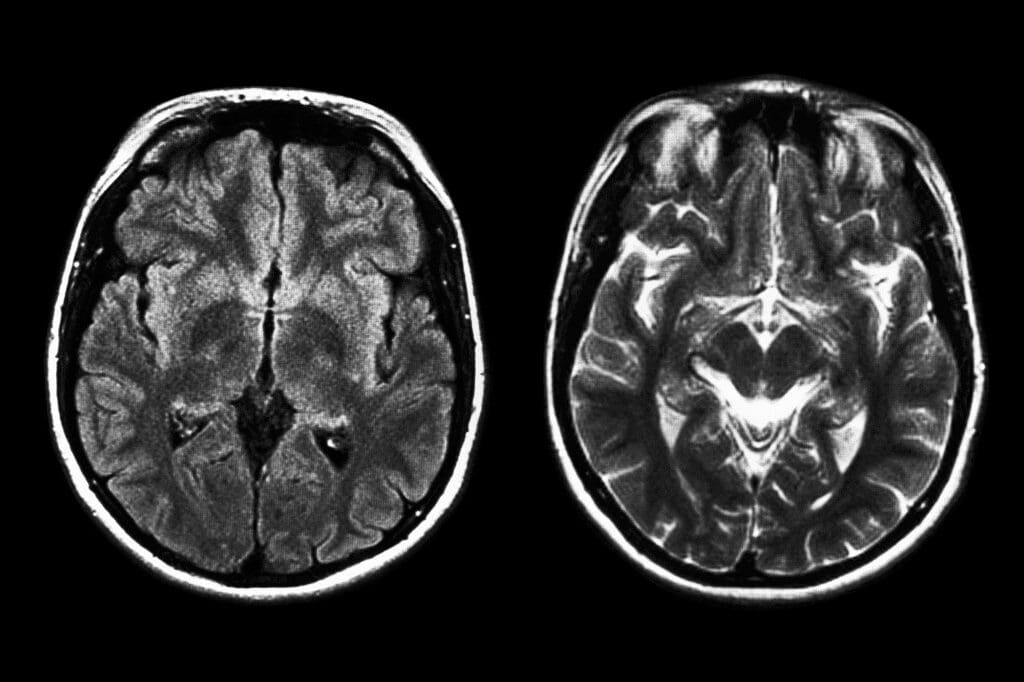

Investigadores de la Universidad de Stanford presentaron un avance significativo en el campo de la neurociencia y la tecnología médica: un dispositivo de interfaz cerebro-computadora (BCI) que convierte pensamientos en palabras escritas. El sistema fue diseñado para personas con parálisis severa o con pérdida del habla, brindándoles una herramienta que les permita comunicarse directamente sin necesidad de vocalizar.